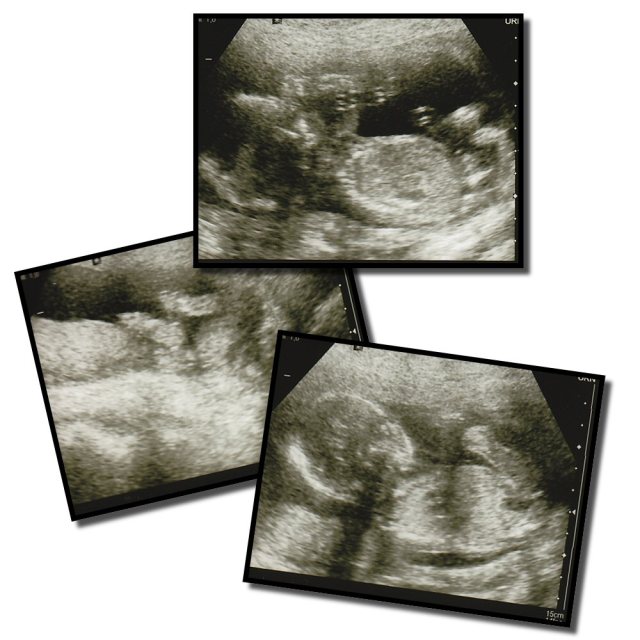

Efter det så var det till att gå över gatan in till MVC och vi stiftade åter bekantskap med kära Ulla! Ultraljudet gick bra och beräknad förlossning flyttades från 14/8 till 12/8 så det var inte så stor skillnad där.

Liten sprattlade och for runt så Ulla hade emellanåt riktigt jobbigt att få till bra bilder för att mäta. Moderkakan visade sig sitta högt upp bak så det kommer bli tydliga sparkar fram igenom…. precis som med Ian. Förövrigt såg allting bara jättebra ut med bebis!

Däremot så lurade magkänslan oss totalt, jag hade varit övertygad om att det var en flicka och Teskedspappan hoppades väl han med så smått, men lång näsa fick vi… det är ett pungdjur till! Oskarström kommer invaderas av galna Hjelmbröder om 10 år…